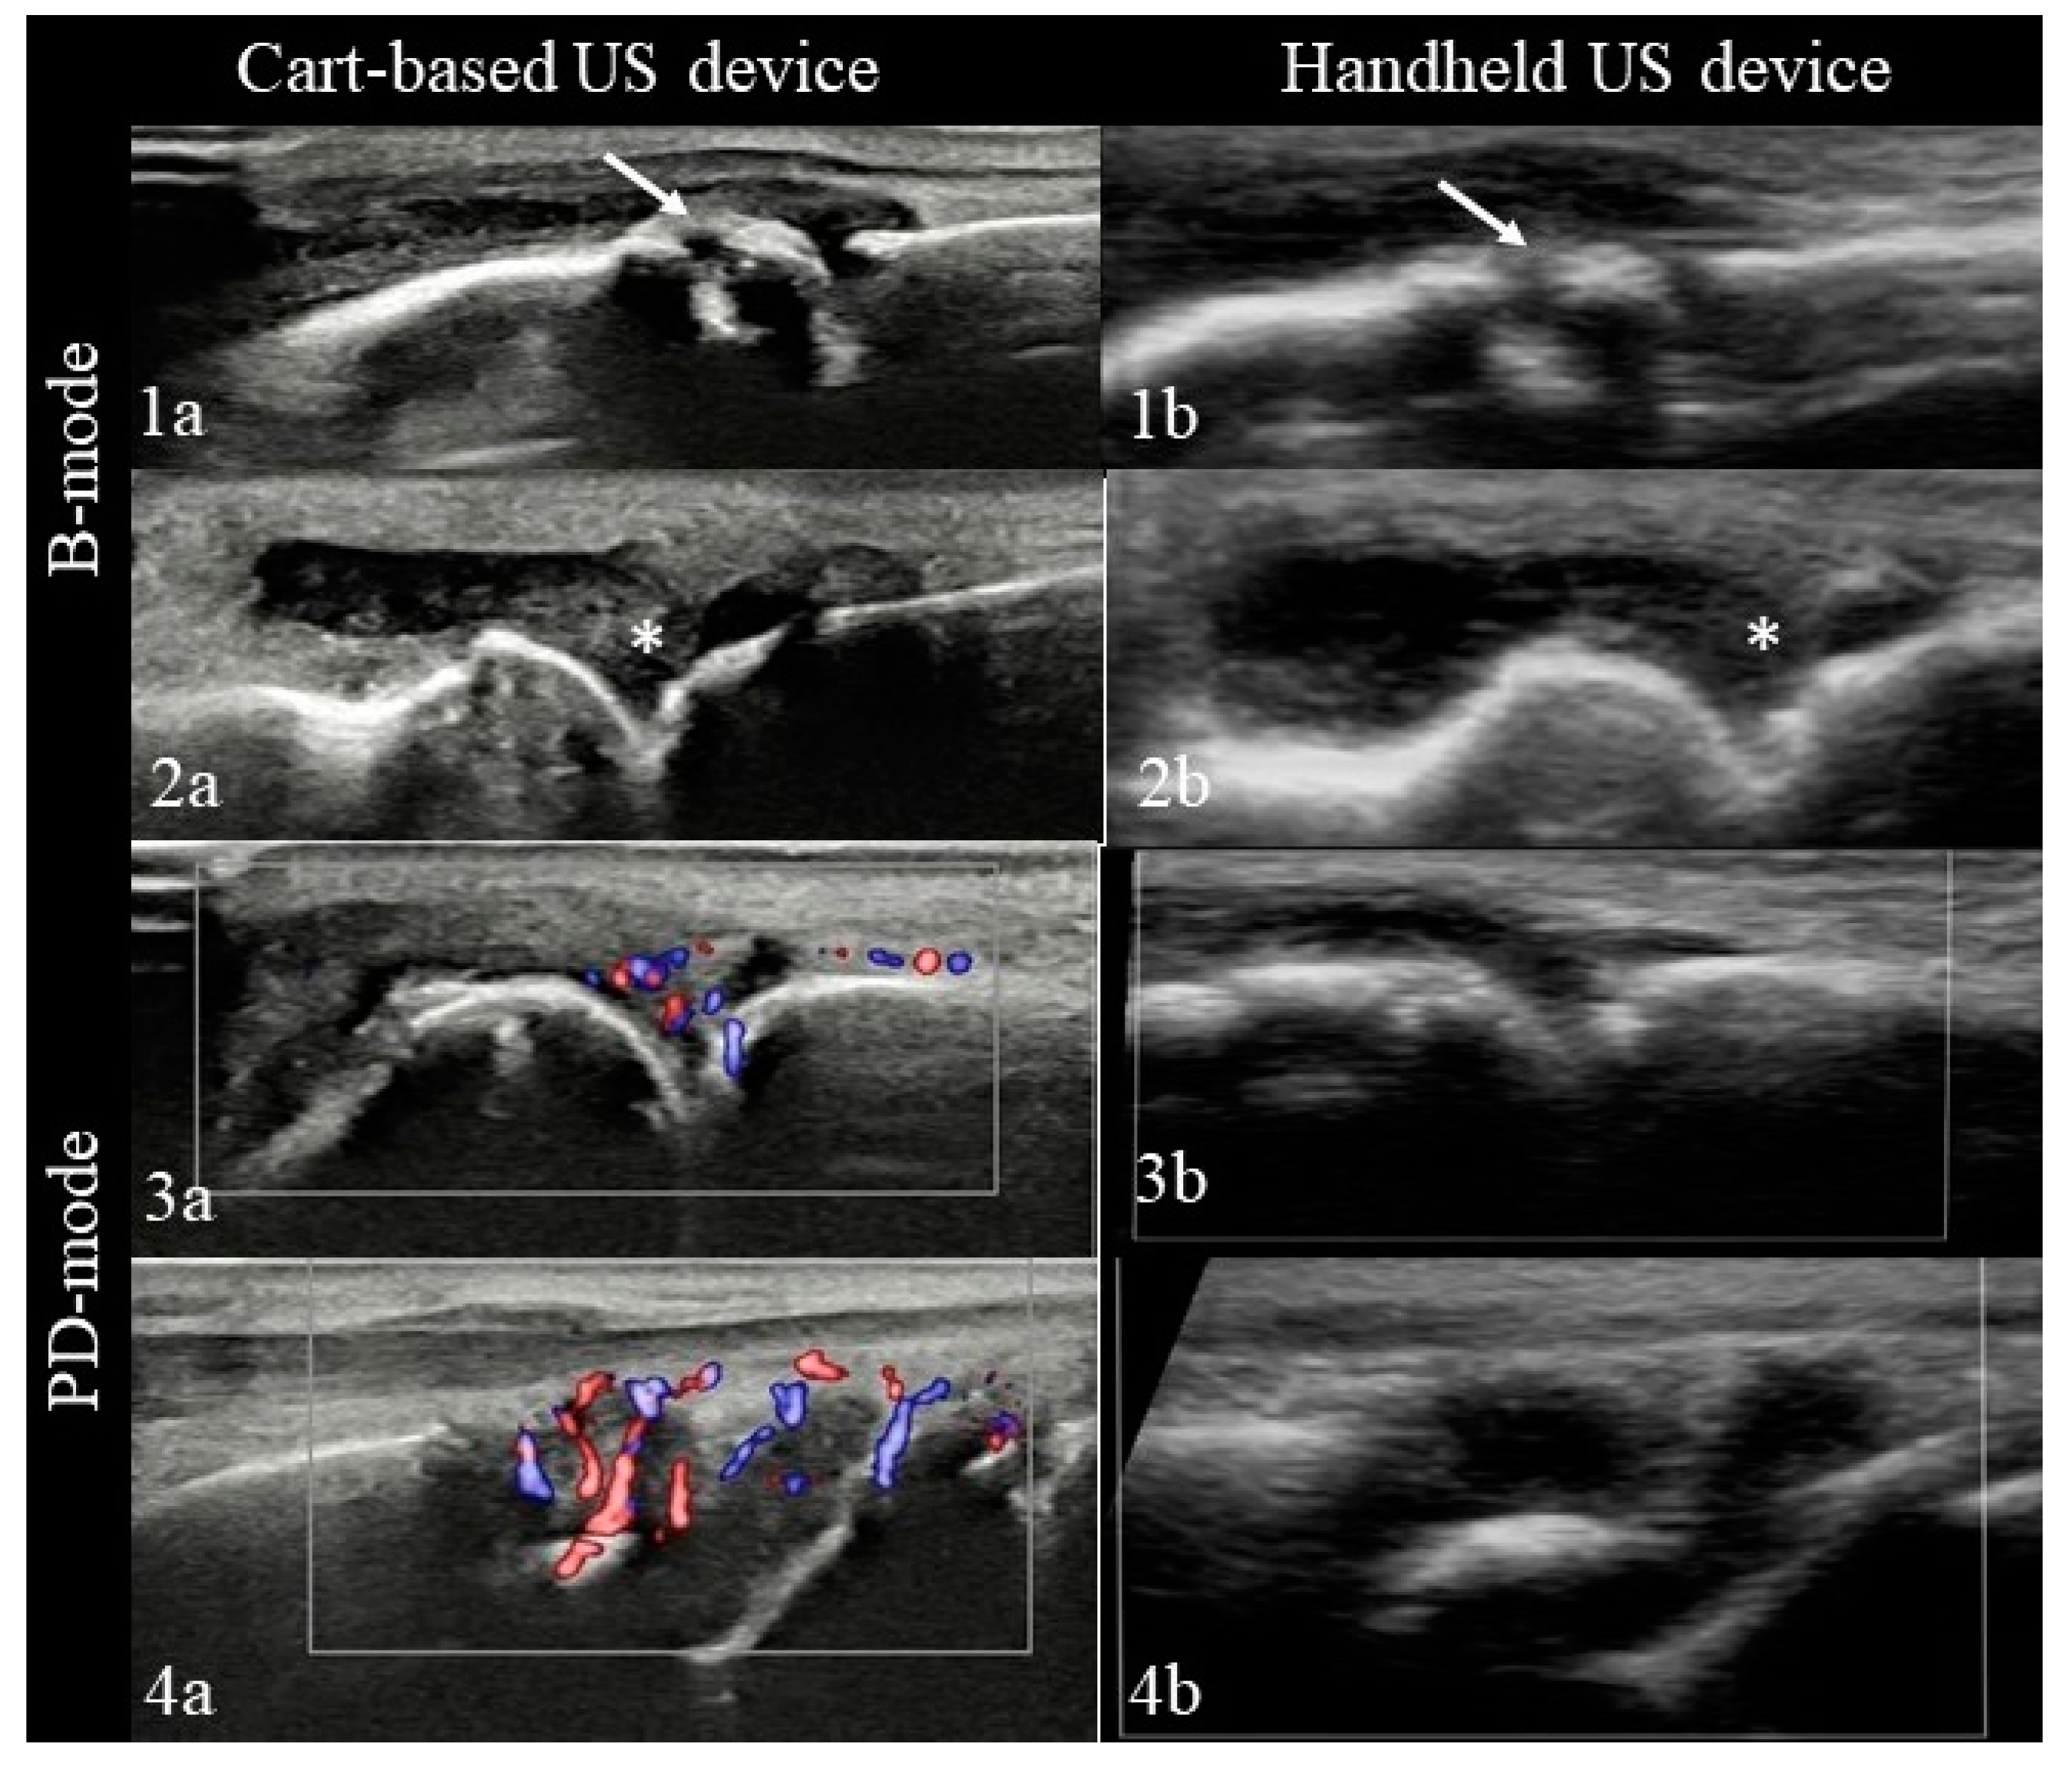

3.2. Ultrasound Examination

- B mode assessment

- Power-Doppler assessment